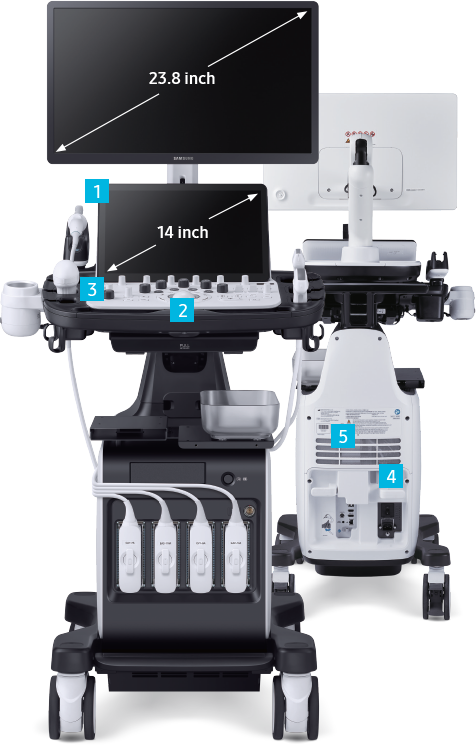

Sistemul cu ultrasunete V8 prezintă o calitate excelentă a imaginii bazată pe arhitectura inovatoare Crystal și asigură eficiență și simplitate maximă datorită instrumentelor Intelligent Assist și unui flux de lucru reproiectat pentru a satisface toate nevoile mediului clinic. Designul sofisticat și ergonomic evidențiază designul atent al Samsung, acordând o atenție deosebită confortului de utilizare, prioritate absolută pentru experiența produsului. Căutăm constant noi modalități de a ajuta profesioniștii să atingă cel mai înalt nivel de calitate a diagnosticului, cu o claritate mai mare a imaginii , o mai mare acuratețe și o eficiență mai bună a muncii.

Simplificați-vă ziua prin eficientizarea fluxului de lucru cu funcțiile convenabile și soluțiile inteligente ale V8 care reduc sarcinile multiple la doar câțiva pași și apăsări convenabile de taste. Datele scanate reprezentate într-un mod simplu și precis reprezintă un aspect important considerat pentru a îmbunătăți experiența utilizatorului, precum și designul ergonomic exploatează eficient mediul de lucru al utilizatorului și garantează utilitate și productivitate.